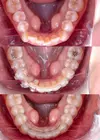

Tooth Decay

Tooth and Gum Diseases